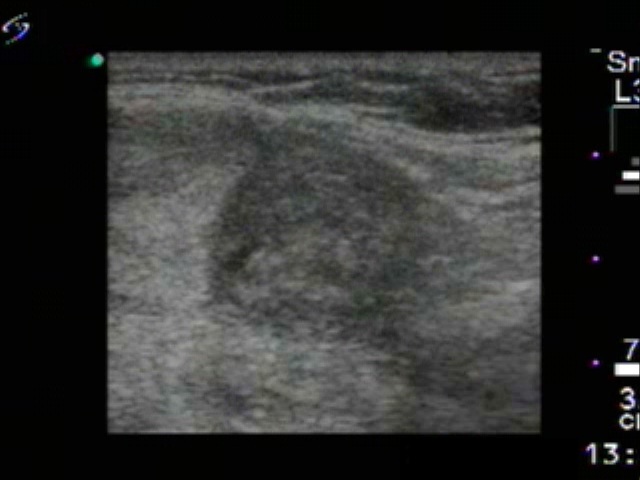

Ethanol sclerotherapy: non-toxic solid nodules - Case 3

First session of therapy (ultrasonographic picture 5)

Lower part of the right lobe, another longitudinal scan. The smaller hypoechogenic nodule is demonstrated.